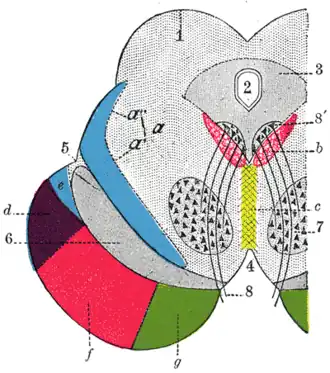

In a coronal section through the middle of the lentiform nucleus, two medullary laminae are seen dividing it into three parts.

The lateral and largest part is of a reddish color, and is known as the putamen, while the medial and intermediate are of a yellowish tint, and together constitute the globus pallidus; all three are marked by fine radiating white fibers, which are most distinct in the putamen.

Schematic representation of the chief ganglionic categories (I to V)

Schematic representation of the chief ganglionic categories (I to V) -